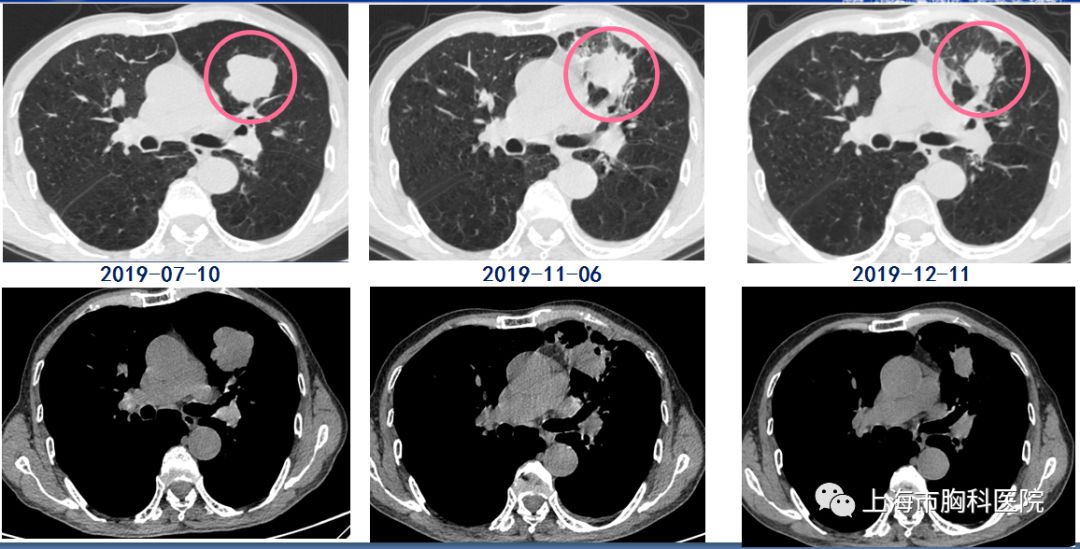

经过三个周期的治疗,病灶明显缩小

当日,由孙加源主任带领介入呼吸病团队进行介入手术。医生们实施穿刺后精准定位,成功对目标病灶进行了冷冻消融。同步,患者也在医生的指导下进行免疫用药治疗。经过三个周期的治疗后,复查患者CT发现,主病灶从4公分大小,已经缩小了40%以上!联合治疗效果显著,老先生能够自如活动,精气神也较之前好了许多。